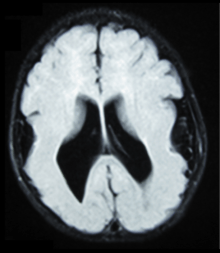

Neuronal migration disorder

Neuronal migration disorder (NMD) refers to a heterogenous group of disorders that, it is supposed, share the same etiopathological mechanism: a variable degree of disruption in the migration of neuroblasts during neurogenesis.[1] The neuronal migration disorders are cerebral dysgenesis, brain malformations caused by primary alterations during neurogenesis; on the other hand, brain malformations are highly diverse and refer to any insult to the brain during its formation and maturation due to intrinsic or extrinsic causes that ultimately will alter the normal brain anatomy. However, there is some controversy in the terminology because virtually any malformation will involve neuroblast migration, either primarily or secondarily.

NMDs occur in the instance that 1) neuroblasts do not migrate from all of the ventricles or migrate only part of the way, 2) only some of the neuroblasts reach the cortical layer, 3) neuroblasts overshoot the appropriate cortical layer and protrude into the subarachnoid space, or 4) the late stage organization of the neuronal layer in the cortex is disrupted. Abnormal migration ultimately results in abnormal gyral formation.[2]